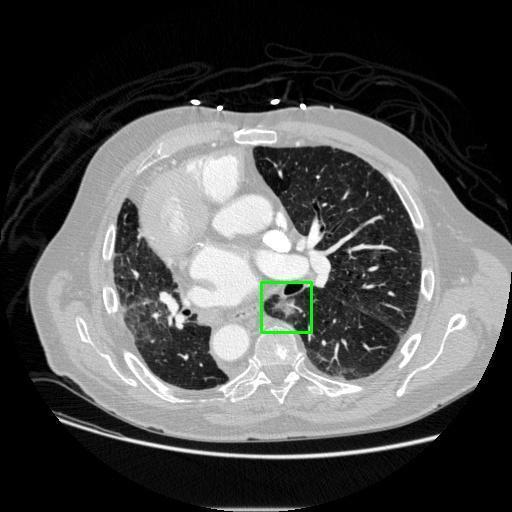

We developed an AI-based system using deep learning models for analyzing lung CT scans to detect and classify pulmonary nodules. We chose the YOLOv11 architecture for its enhanced object detection capability and adapted it specifically for medical imaging, incorporating pixel-level precision and severity classification.

Classification into three severity levels with colored bounding boxes.

Designed a severity classification system that categorizes nodules into null, moderate, and severe using colored bounding boxes, assisting in rapid clinical decision-making.